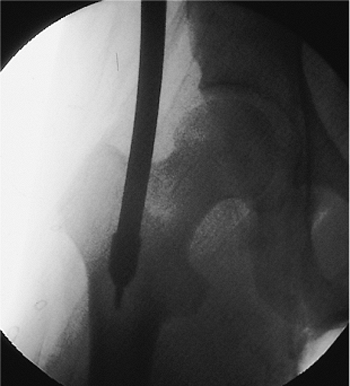

A guide pin is placed in the piriformis fossa, and its position is

confirmed with fluoroscopy. The tip should be centered directly in-line

with the medullary canal as seen in both the AP and lateral views.

Medial portal placement should be avoided because it may cause a

femoral-neck fracture. Portal placement laterally may lead to

comminution and varus alignment in proximal fractures. Once the pin is

properly positioned in the piriformis fossa and is confirmed

fluoroscopically, the femur is opened with a cannulated drill. In an

alternative, an awl may be placed in the piriformis fossa and the

proximal femur opened by hand (Figs. 21.12,21.13,21.14,21.15,21.16,21.17,21.17,21.18,21.19,21.20)

![]() |

|

Figure 21.13.

Femoral entry portal establishment with cannulated drill. As shown here, a 5/32 inch Steinmann pin is guided radiographically and drilled into the piriformis fossa. |

Figure 21.14.

Steinmann-pin placement. The correct position of the Steinmann pin as it enters the top of the femur at a point where the line defining the center of the medullary canal would emerge from the top of the bone. |

Figure 21.15.

Steinmann-pin placement. As in the AP view, the lateral view of the proximal femur shows that the 5/32 inch Steinmann pin penetrates the bone exactly at a point where the line defining the center of the medullary canal emerges from the top of the bone. |